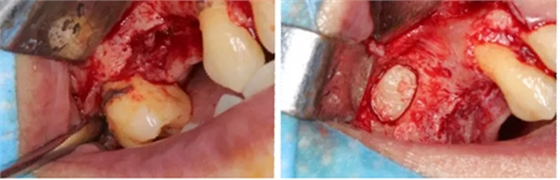

術后8個月 術后10個月